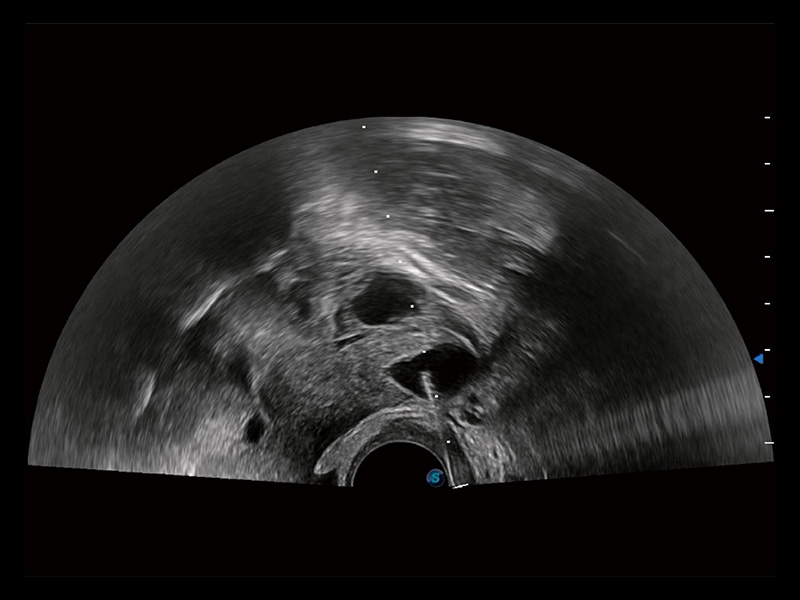

卵巢多囊样改变

子宫内膜息肉

输卵管间质部妊娠